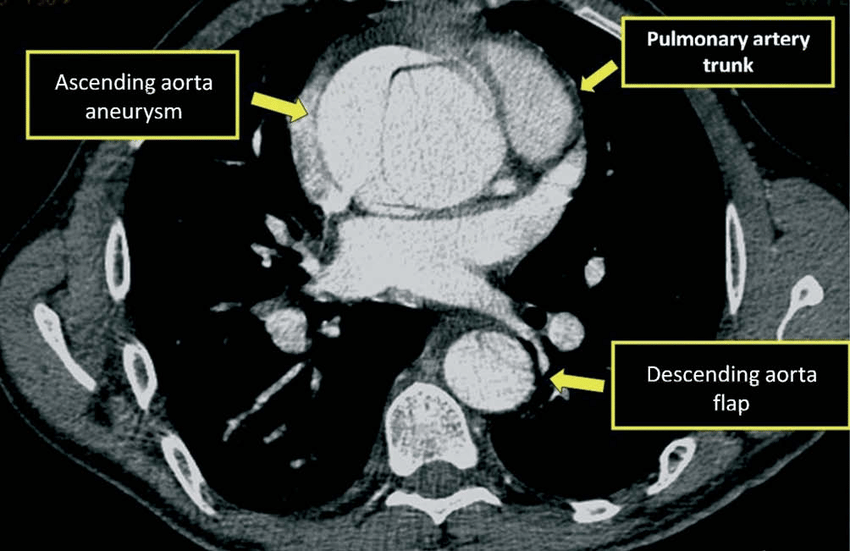

One unique thing about CT scans is the ability to perform a test with and without contrast. Contrast is usually an iodine-based fluid that is taken by IV or mouth to allow a specific organ to appear more defined up on CT scan. This is very helpful in aortic dissections where contrast may help us distinguish between the true and false lumens (true is lighter due to contrast)!